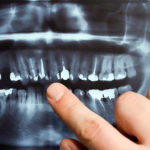

Composite Fillings are also called as tooth-colored fillings because of its natural look. It is used to repair teeth that are damaged by decay, cracks, fractures, or chips. Composite fillings provide durability and resistance to fractures for the teeth to withstand the pressure and constant stress of chewing when eating. It can be used on both front and back teeth. Tooth-colored Fillings are an ideal dental solution for patients who want to restore and repair their damaged teeth while maintaining a natural look.

- The dentist will numb the area where the filling shall be placed and then drill the tooth with either an air abrasive instrument or a laser to remove the decayed portion of the teeth.

- The treated space will then be cleaned thoroughly and prepared for the placement of the filling.

- If the decayed area is near the tooth root, the dentist will apply a special medication to provide added protection.